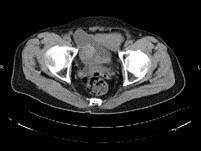

问题 男,74岁,无痛性肉眼血尿1个月余,CT扫描如图所示,该疾病最可能的诊断为 ( )

选项 A、膀胱息肉 B、输尿管囊肿 C、膀胱结石 D、膀胱血块 E、膀胱癌

答案 E